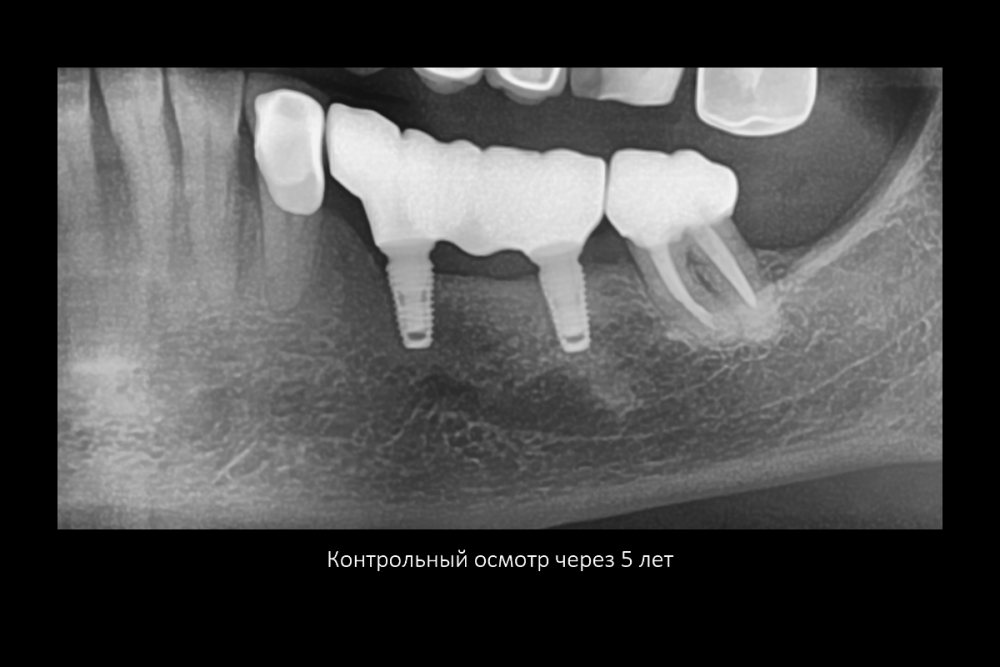

Карен Аванесов Опубликовано 11 февраля, 2022 Поделиться Опубликовано 11 февраля, 2022 все на слайдах. 2 Ссылка на комментарий

Карен Аванесов Опубликовано 12 февраля, 2022 Автор Поделиться Опубликовано 12 февраля, 2022 15 часов назад, АнтонТЛТ сказал: Я при таких сюрпризах делаю мобилизацию язычного лоскута, вестибулярный не мобилизирую, фдм вторым этапом. Что на 4 слайде справа? Делал и так ка ты написал. коллаген 15 часов назад, Irouil сказал: Кажется, там какой-то алографт на который сверху подсыпан ксено можно ли проследить вывод из работы, что лучше «без», чем «с»? Именно! и не только. Полезно смотреть старые работы. только не все пациенты исправно приходят Ссылка на комментарий

Карен Аванесов Опубликовано 15 февраля, 2022 Автор Поделиться Опубликовано 15 февраля, 2022 13.02.2022 в 22:56, Fin сказал: Карен. Подскажите пожалуйста. Правильно ли я понял, что в на данный момент в такой ситуации (оголение импланта с вестибулярной стороны на половину) Вы бы обошлись просто установкой импланта + ССТ вестибулярно? Да, именно так. 14.02.2022 в 10:33, Bier сказал: от подобной присыпки толку обычно нет. Олег, помнишь аник "темно здесь..." Вот только не начинай про полужесткие сосиски)))) Но ты прав или делпать по отработанной технологии или никак 1 Ссылка на комментарий

Карен Аванесов Опубликовано 15 февраля, 2022 Автор Поделиться Опубликовано 15 февраля, 2022 13.02.2022 в 22:56, Fin сказал: Карен. Подскажите пожалуйста. Правильно ли я понял, что в на данный момент в такой ситуации (оголение импланта с вестибулярной стороны на половину) Вы бы обошлись просто установкой импланта + ССТ вестибулярно? Это как вариант не на каждый случай конечно , но когда по делу все работает. Ссылка на комментарий